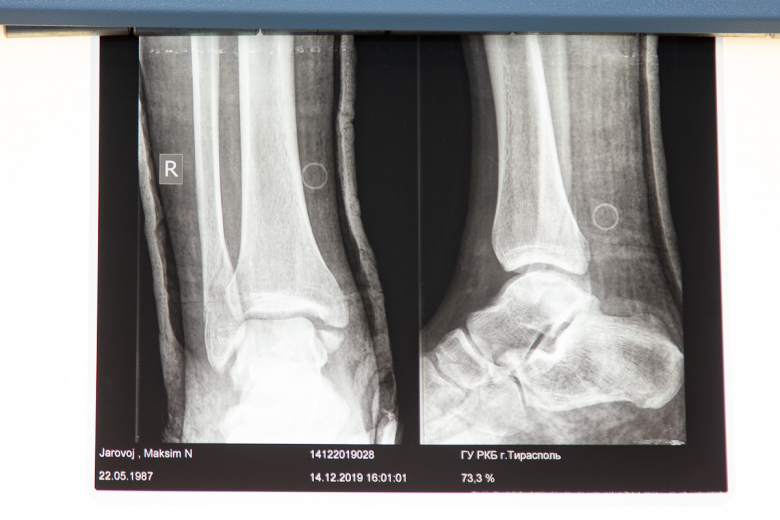

В кабинете, где проходит первичный осмотр, поставили негатоскоп: на светящемся экране врач может детально рассмотреть снимок из рентген-кабинета. Его уже не нужно распечатывать - доступна электронная версия.